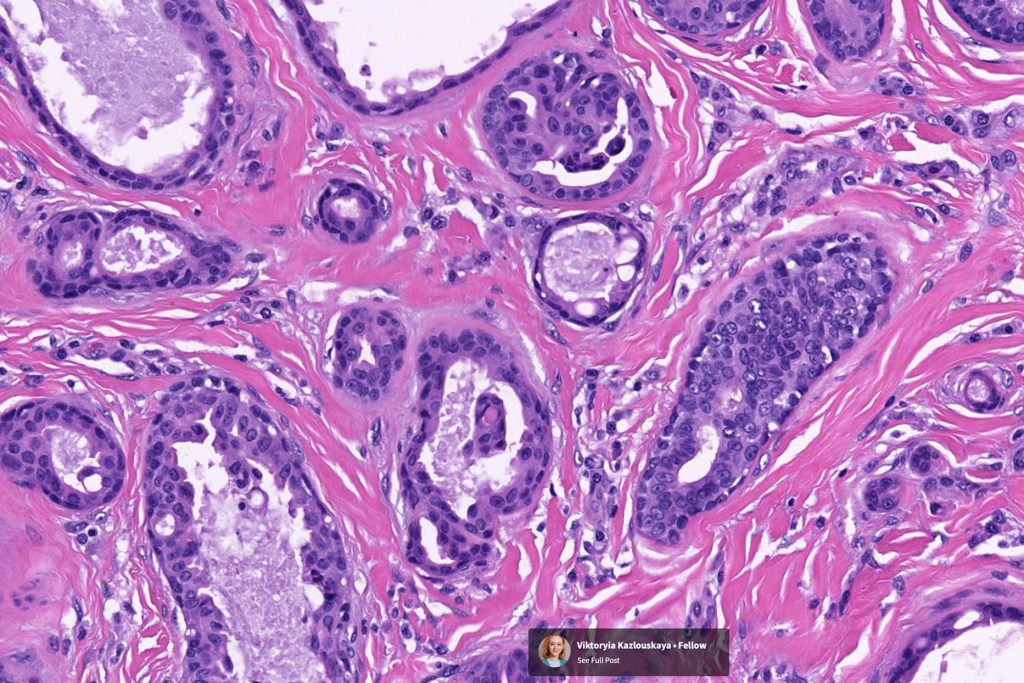

•Circumscribed nodule composed of ducts & cysts embedded in a dense fibrous stroma sometimes associated with lymphoid aggregates/germinal centers

•Ducts lined by double-layered epithelium- small inner, uniform cells with eosinophilic cytoplasm & vesicular/hyperchromatic nuclei with small nucleoli & outer myoepithelial cells

•No pleomorphism and mitoses are sparse of absent

•Pseudo-papillae (devoid of a fibrovascular core) are often conspicuous

Absense of true papillae (i.e with a fibrovascular core)

•Variable cribriform pattern